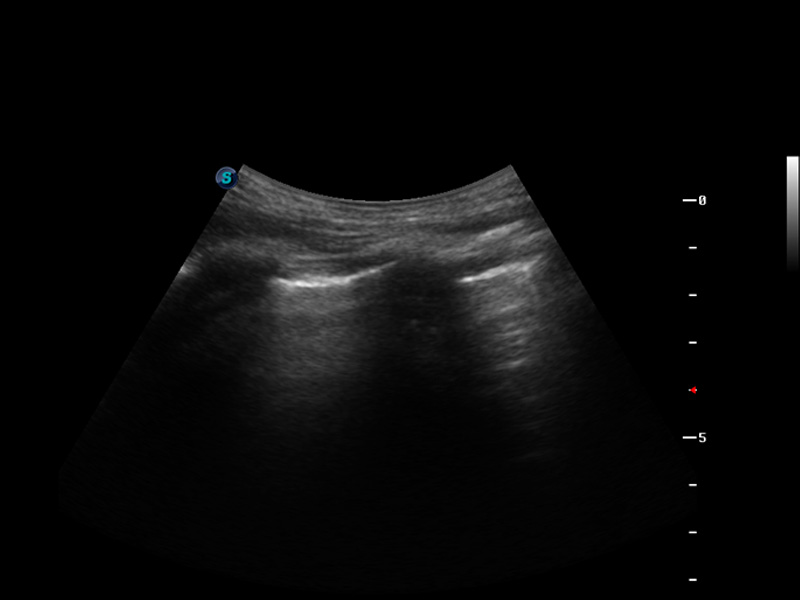

S9便携式彩色多普勒超声诊断仪是球速体育入口研发的高端便携彩超设备,外观设计新颖、产品性能卓越。S9在便携超声领域采用了突破传统的触摸屏交互设计,并以先进的软件硬件技术和设计理念,为您带来清晰的图像质量、稳定的工作性能和便捷的操作体验。

μ-Scan微米成像